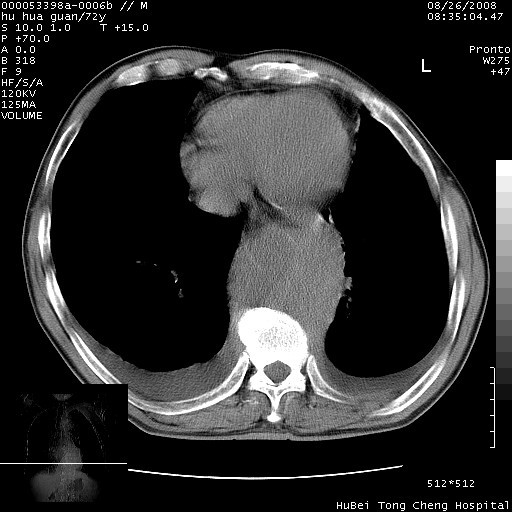

主动脉瘤?

考虑胸主动脉下段夹层破裂。

考慮夾層動脈瘤破裂可能,建議增強掃描。

可以明确的说。肯定不是主动脉夹层破裂出血!考虑为淋巴瘤或间叶组织来源的恶性肿瘤可能性大。右肺小结节建议薄层观察,如能发现恶性征象,那椎前改变就考虑为转移所致。至于双侧少量胸水乃静脉血回流受阻所致。

降主动脉前移位,后纵隔占位

后纵隔占位,降主动脉前移位;双侧胸腔积液;应排外食管病变侵犯血管可能;

主动脉瘤破裂

建议排除结核引起的冷脓肿。